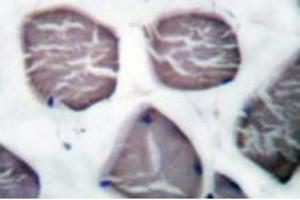

Dieser Kaninchen Polyklonal Antikörper detektiert spezifisch Estrogen Receptor alpha in WB, IHC (p) und EIA. Es zeigt Reaktivität gegenüber Proben von Human.

Western Blotting (WB), Immunohistochemistry (Paraffin-embedded Sections) (IHC (p)), Enzyme Immunoassay (EIA)